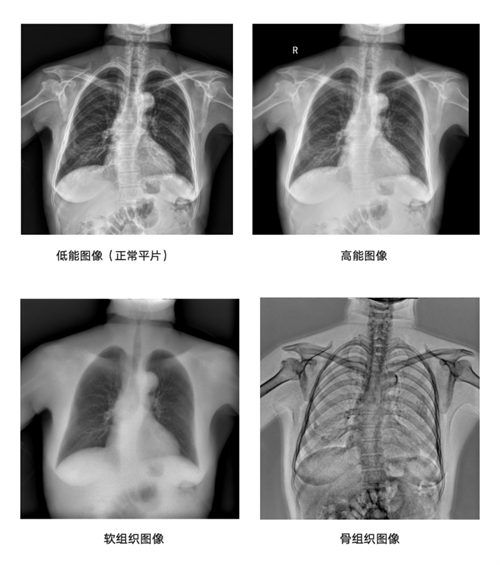

双层动态平板探测器则进一步拓宽了动态影像的应用边界。与传统的单层闪烁体结构探测器不同,安健科技自主研发的多层闪烁体结构探测器可以实现基于DR技术的能谱成像。它具备两层碘化铯涂层,可以自动吸收X光的高能和低能信号,一次曝光即可获取常规、低能、高能三张图像。与需要两次曝光才能获取高低能的影像相比,安健科技的能谱技术可以一次曝光获取三种影像,因此具备同时、同向特点,避免了配准问题和运动伪影。并且,其剂量与常规平片相近。在胸部摄影中,骨骼抑制图像可以让肺实质结节,软组织抑制图像则能清晰显示肋骨骨折与骨转移灶。在创伤急救中,一次拍摄即可评估诊断骨折情况与软组织损伤程度。